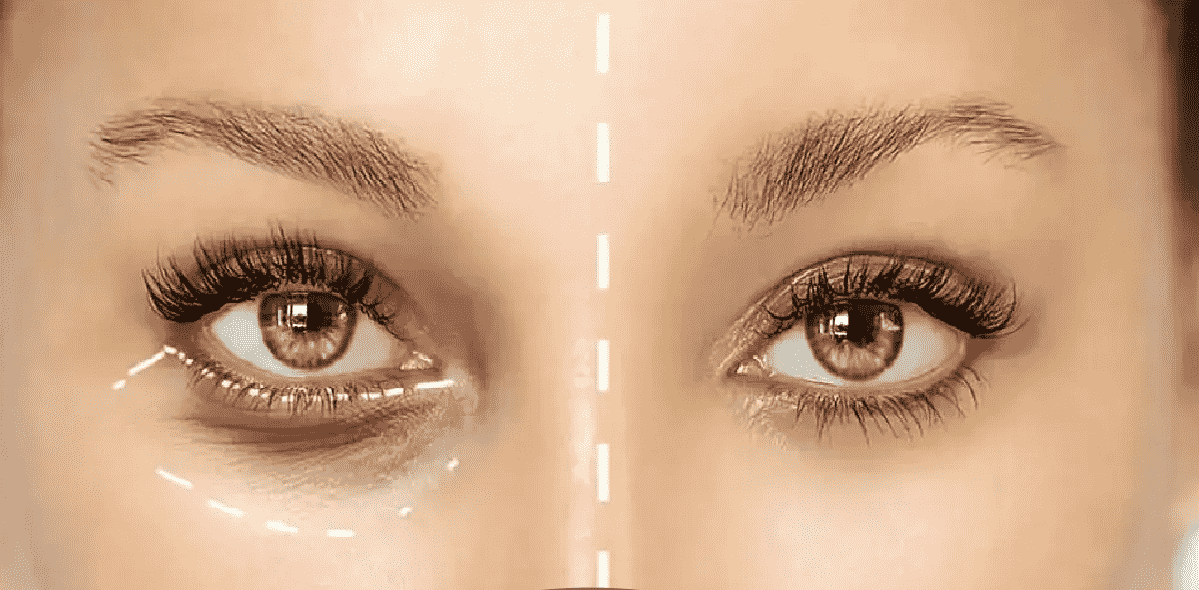

چگونه تیرگی دور چشم را در سه روز برطرف کنیم؟

تیرگی دور چشم یکی از مشکلات رایج پوستی است که بسیاری از افراد با آن مواجه هستند. این مسئله می…